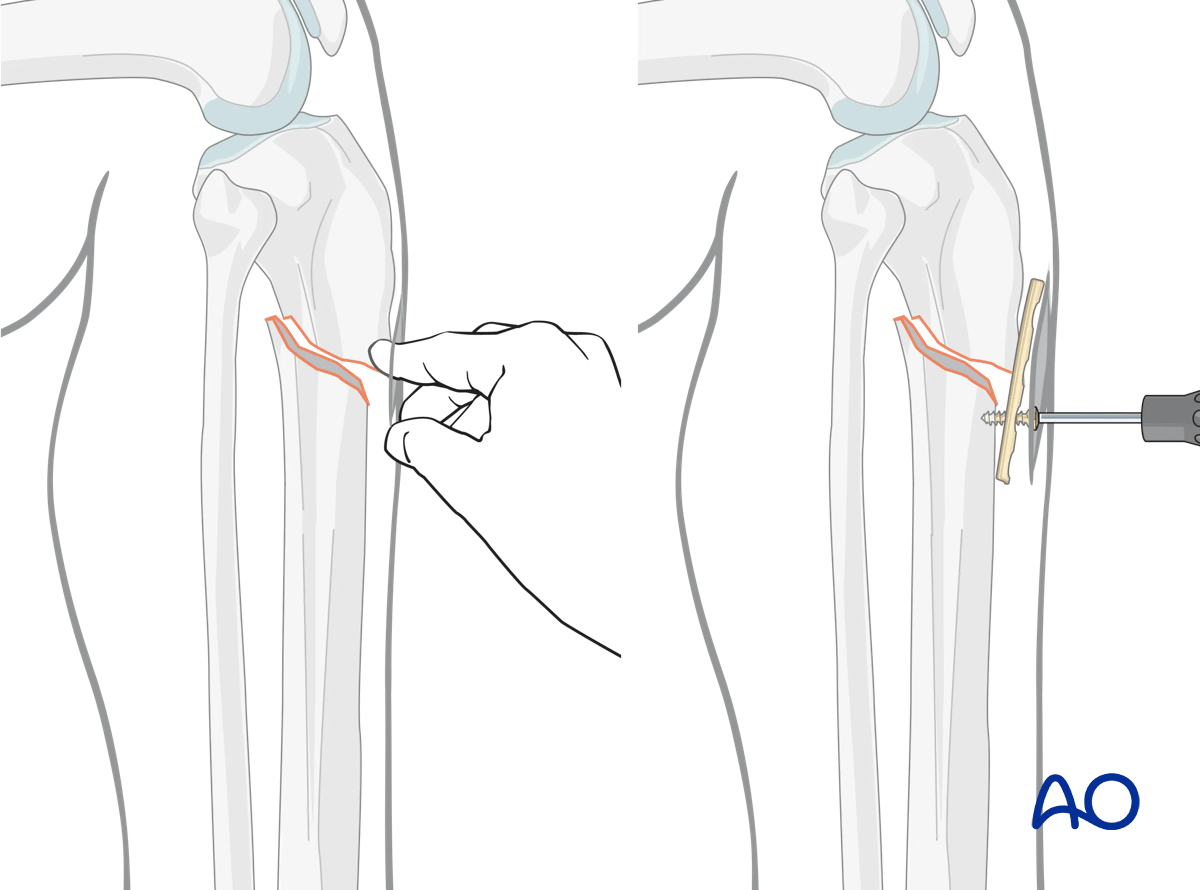

Plate as reduction aid

It may be difficult to achieve and maintain reduction in proximal tibia fractures.

As illustrated, a small plate with unicortical screws can be used, both as a reduction aid and to hold the reduction during nail insertion.

This is an open technique, but little soft-tissue dissection is required. The plate can be left in place after the nail is inserted.

Lateral parapatellar intramedullary nailing of the tibial shaft, Reduction and preliminary fixation

Fixing a straight plate into the distal tibial fragment pushes the proximal fragment into alignment, thus correcting the gap and apex-anterior angulation. Adding a proximal screw increases stability, helping to avoid redisplacement during nail insertion.